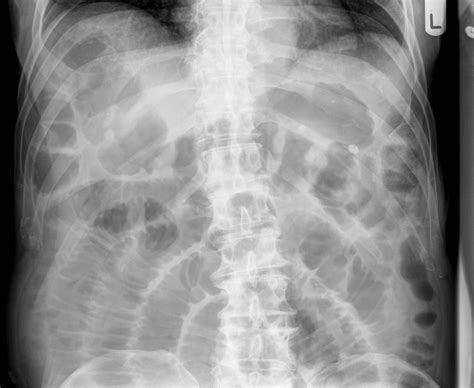

The results of a Small Bowel Series are interpreted by a radiologist, who looks for signs of abnormalities in the small intestine. Some of the conditions that can be detected include:

• Inflammatory Bowel Disease (IBD): Conditions like Crohn’s disease can cause inflammation and ulcers in the small intestine.

• Celiac Disease: This autoimmune disorder can damage the lining of the small intestine, affecting nutrient absorption.

• Intestinal Obstructions: Blockages in the small intestine can be identified, helping to determine the cause and appropriate treatment.

• Tumors and Polyps: Abnormal growths in the small intestine can be detected, which may require further investigation or treatment.

The radiologist will provide a detailed report to the referring healthcare provider, who will then discuss the findings and next steps with the patient.